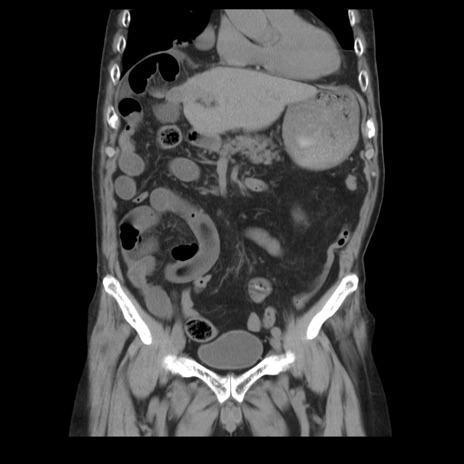

横断像

【症例】70歳代男性

【主訴】腹痛

【現病歴】肝硬変・肝細胞癌にてかかりつけの方。約9時間前に食後より腹痛出現。症状が徐々に増悪し、嘔吐出現したため来院。

【既往歴】肝硬変、肝細胞癌(RFA、TACE後)

【身体所見】意識清明、表情苦悶様、BT 36℃、BP 129/78mmHg、P 88bpm、SpO2 97%(RA)、右上腹部から心窩部にかけて圧痛あり、反跳痛なし、筋性防御あり。

【データ】WBC 5800、CRP 0.16